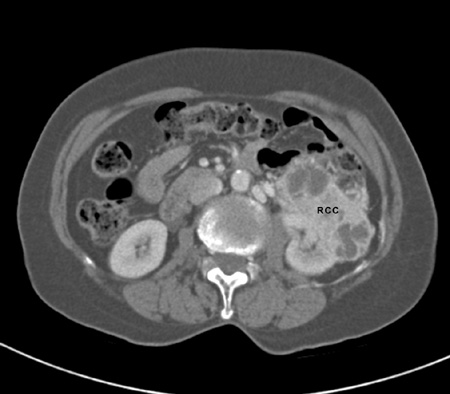

Renal cancer

History

flank fullness, history of dialysis, history of smoking, family history of renal cell carcinoma, polycystic kidney disease, weight loss, exposure to environmental/chemical carcinogens; most cases detected incidentally on imaging

Exam

hypertension, flank mass, adenopathy, new onset of left varicocele, lower extremity oedemas

1st investigation

Metastatic renal cancer

- CT abdomen with and without intravenous contrast:

contrast enhancing renal mass

More

Other investigations

- MRI abdomen/pelvis:

renal mass, regional lymphadenopathy, and/or visceral/bone metastases